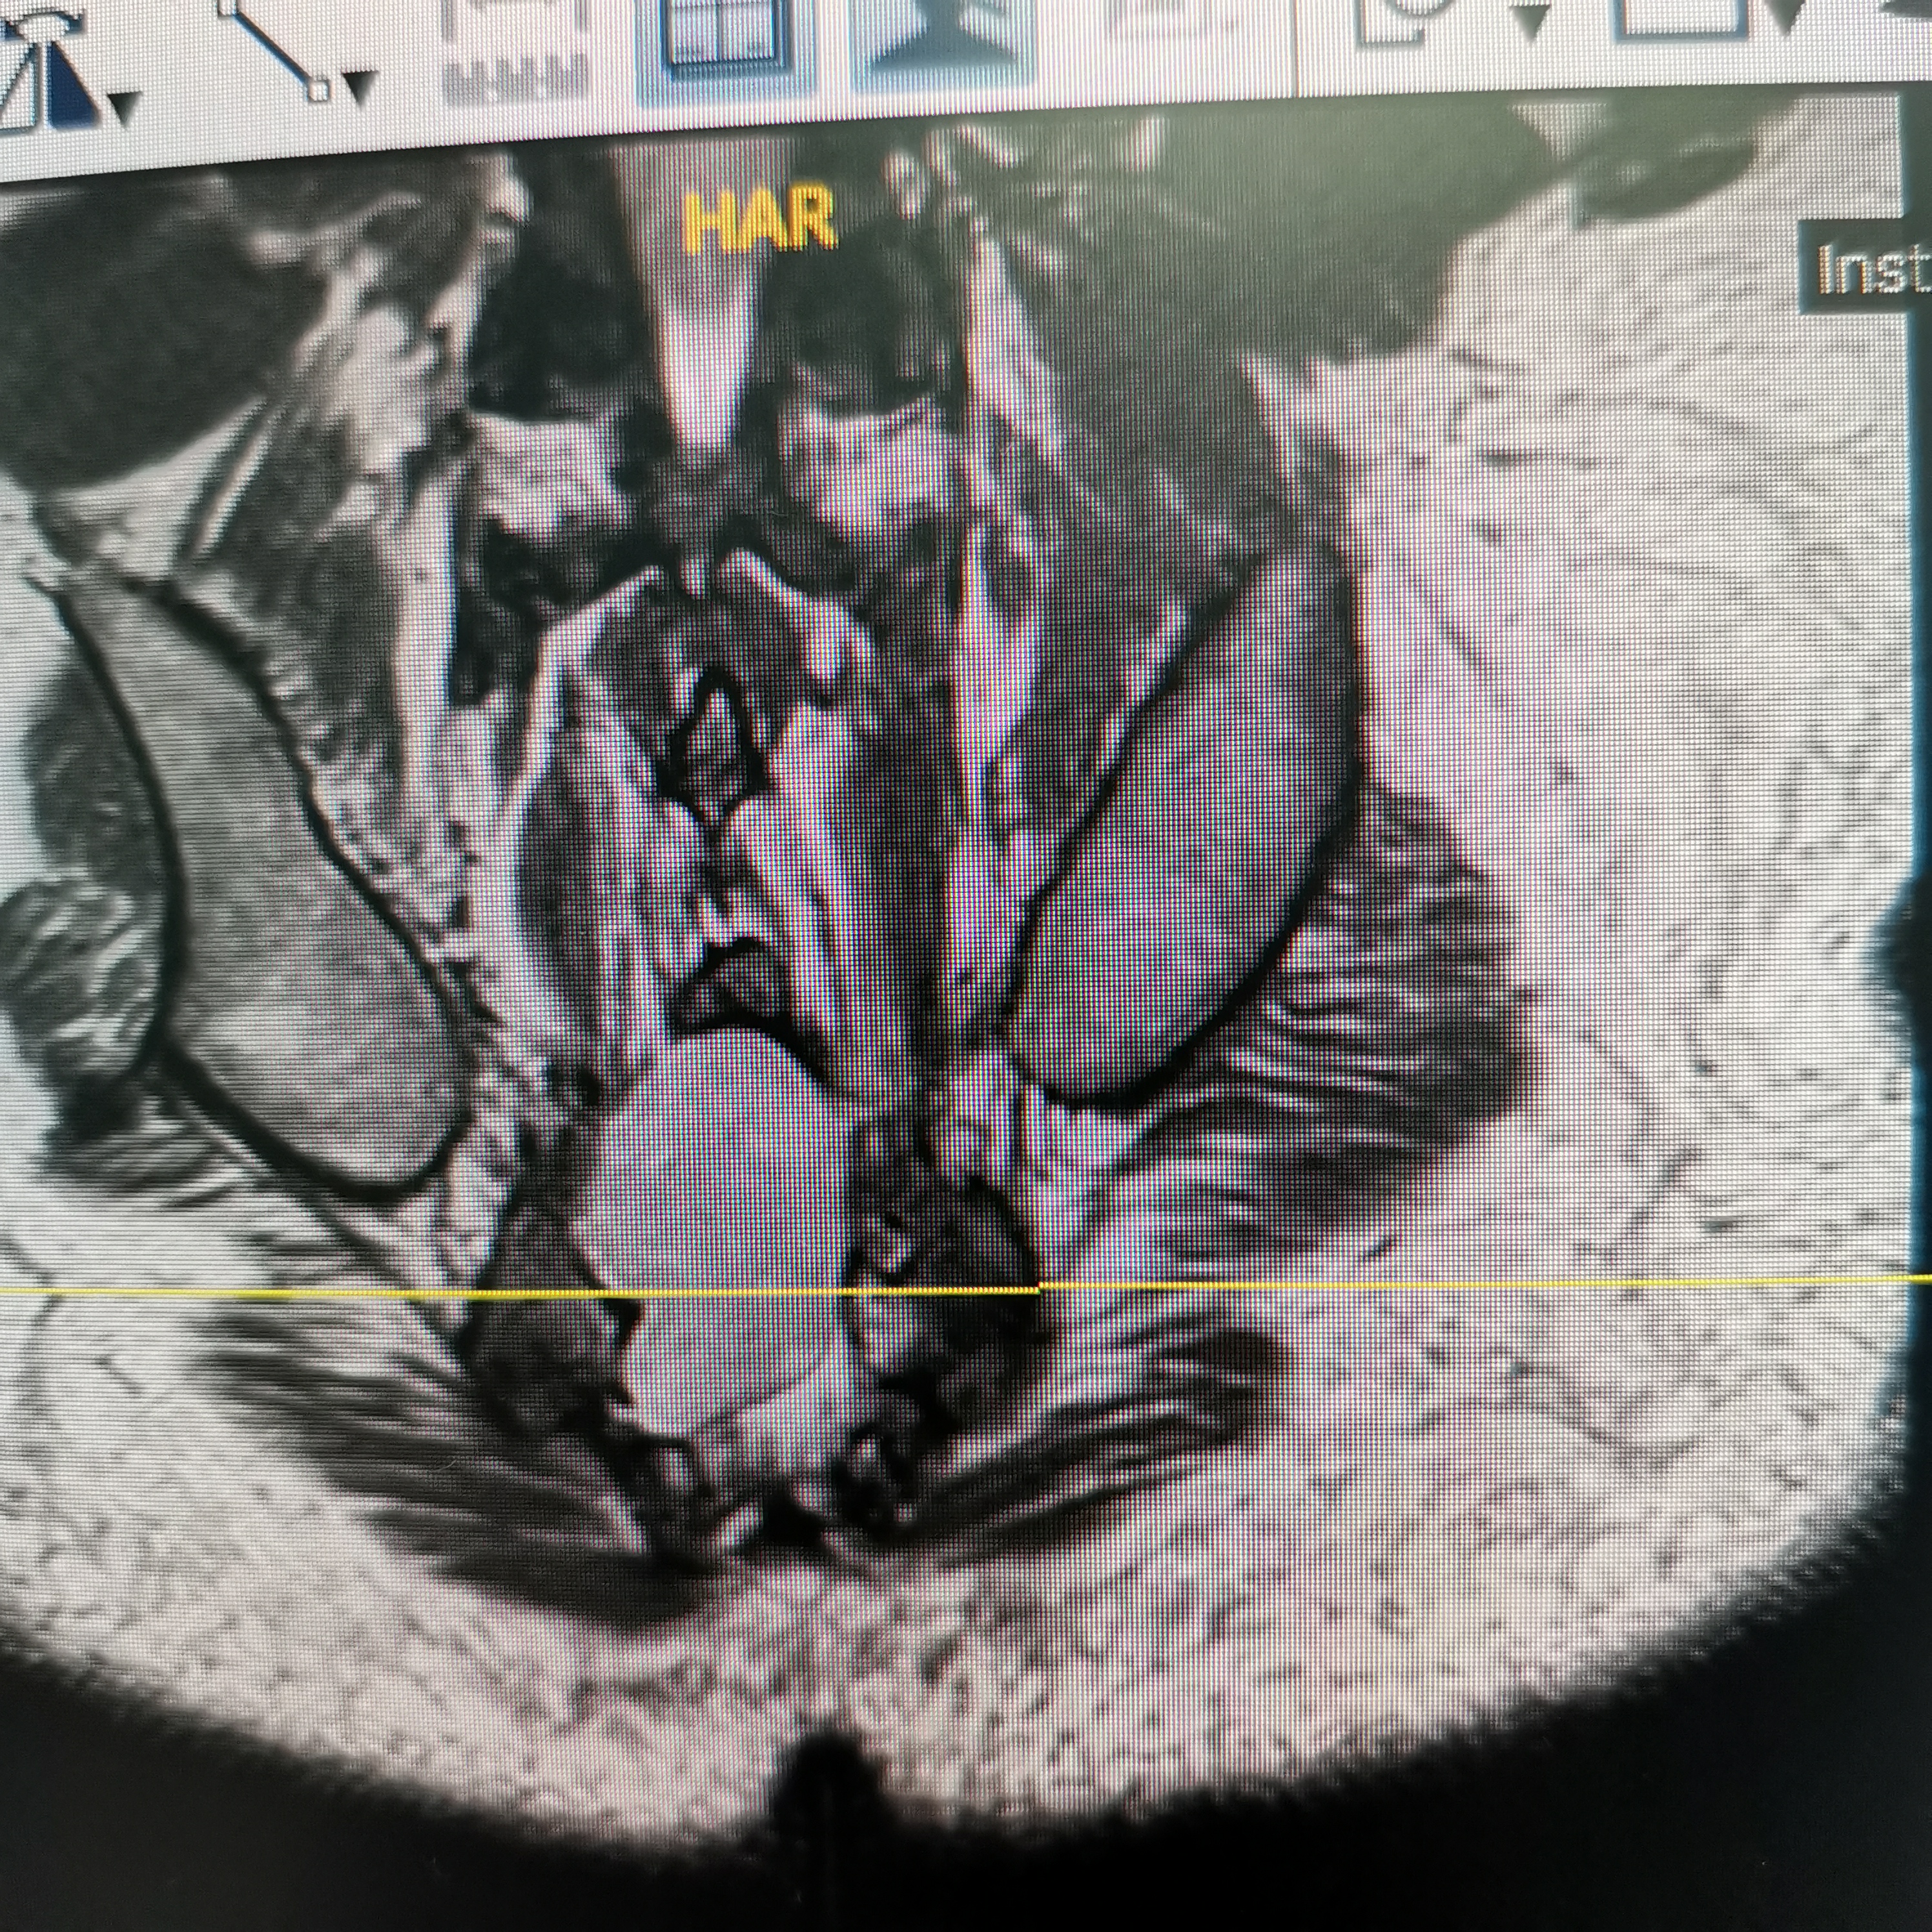

骶椎神经鞘瘤